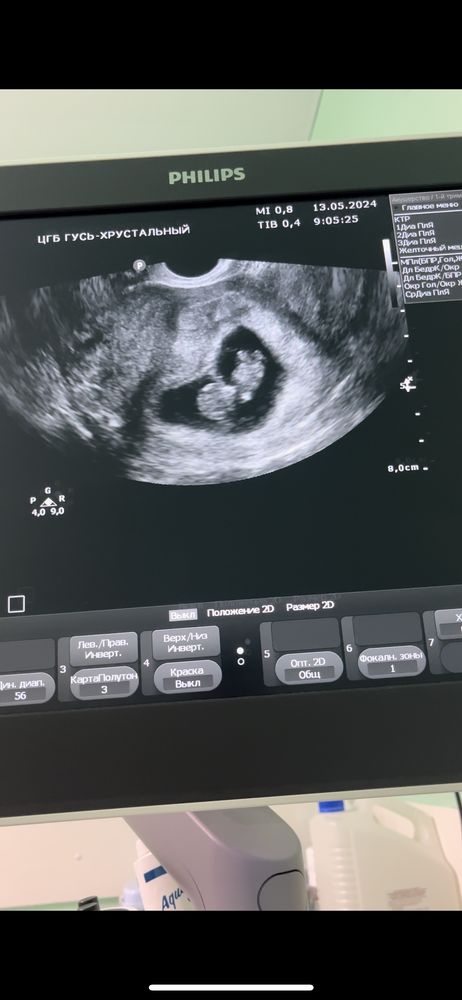

Дарина в Зачатие год Покидайте фото узи в 9 недель 🙏🏻 УЗИ Девочки у кого остались или есть фоточки покидайте пожалуйста! Хочу сходить в 9 неделек на узи, с монитором, хочется узнать как что там примерно видно будет Посмотрите еще 20 записей на эту тему Лучший ответ Елена 9н 2д двойня 02.11.2024 Ответить Отменить Ответить Таня Орозова 01.11.2024 Ответить Екатерина 01.11.2024 Ответить Екатерина Екатерина, чуть больше, 9,5 01.11.2024 Ответить Евгения 9+3 недели 01.11.2024 Ответить ЛисАлис 01.11.2024 Ответить Екатерина 01.11.2024 Ответить Екатерина Екатерина, 9 недель ровно, первое УЗИ 01.11.2024 Ответить Екатерина Екатерина, ножки попка к верху 😄 01.11.2024 Ответить Дарья 01.11.2024 Ответить Евгения Дарья , а вам делали трансвагинально или абдоминально? 01.11.2024 Ответить Дарья Евгения, трансвагинально . А вот 10 недель узи) 01.11.2024 Ответить Евгения Дарья , ух ты) а мне абдоминально делали😁 как в этот раз будут не знаю, пойду в другое место 01.11.2024 Ответить Евгения 01.11.2024 Ответить Мира В интернете нашла)) 01.11.2024 Ответить Девочки подскажите !! Пост нытья Чаты Беременных Выберите чат: Январята-2026 Февралята-2026 Мартята-2026 Апрелята-2026 Майчата-2026 Июнята-2026 Июлята-2026 Августята-2026